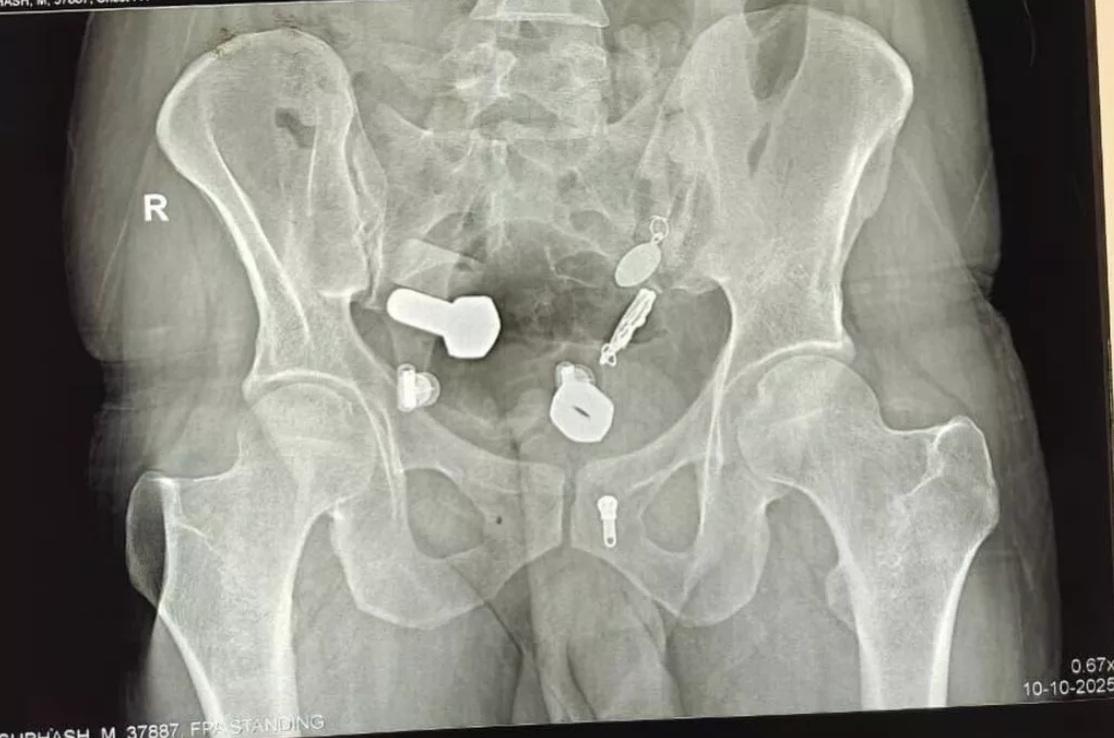

又一異食癖的誇張案例……英國《鏡報》等媒體報道,印度齋浦爾(Jaipur)一名34歲男子因劇烈腹痛、無法飲水進食,本月9日被家人送往醫院急症室就診。醫生替他做X光等檢查,驚見他食道裡竟卡著一隻手錶,大腸裡還有多塊鐵片、螺絲帽、螺絲、繩子、吊墜等物品,讓醫療團隊十分驚訝。

醫療團隊隨即進行長達3小時的緊急微創手術,先在男子腹部開一個小切口,再用儀器將男子食道和腸道裡的所有異物取出。